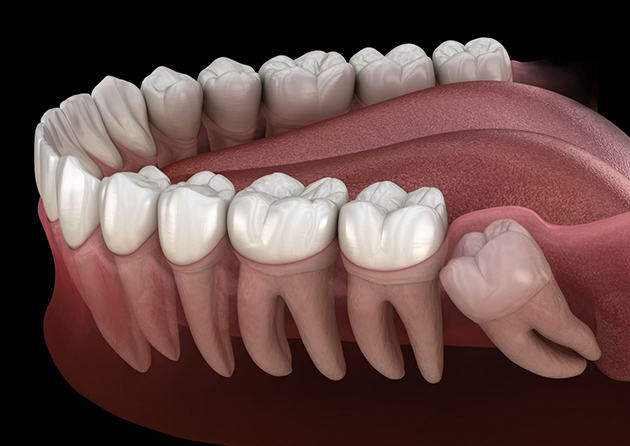

Not sure if you or your teen need your wisdom teeth removed? Get the answers you need before the third molars cause painful and expense orthodontic and periodontal problems down the road!

The wisdom teeth - also known as the third molars - begin causing issues like pain and periodontal and orthodontic issues for many in the late teen years or early 20s.